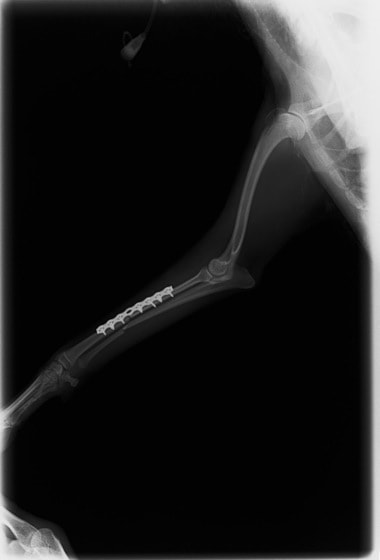

トイプードル 右遠位橈尺骨短斜骨折のALPSによる内固定